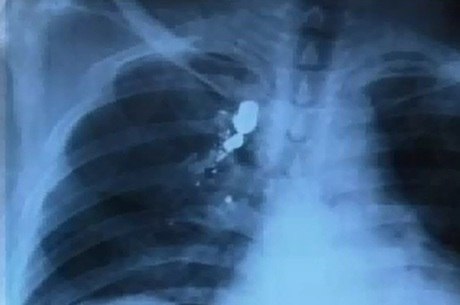

Os problemas são reflexos da bala alojada na coluna. Ele foi vítima de uma tentativa de assalto há cerca de um ano e foi alvejado três vezes. Dois disparos atingiram as costas e outro a mão do pintor.

Mesmo socorrido, os médicos não retiraram nenhuma bala do corpo de Ivan. Por causa do projétil que está perto do polegar, o homem de 42 anos perdeu alguns movimentos da mão e como sempre trabalhou como pintor, teve que aprender outra função para sustentar a família. Ele conta que hoje vive com o que ganha lavando carros.

Segundo o pintor, especialistas já disseram que as balas alojadas nas costas não podem ser retiradas porque são procedimentos de alto risco. Mas ele espera que a da mão seja removida, já que recebeu um encaminhamento médico, mas, há quase oito anos, espera uma resposta.